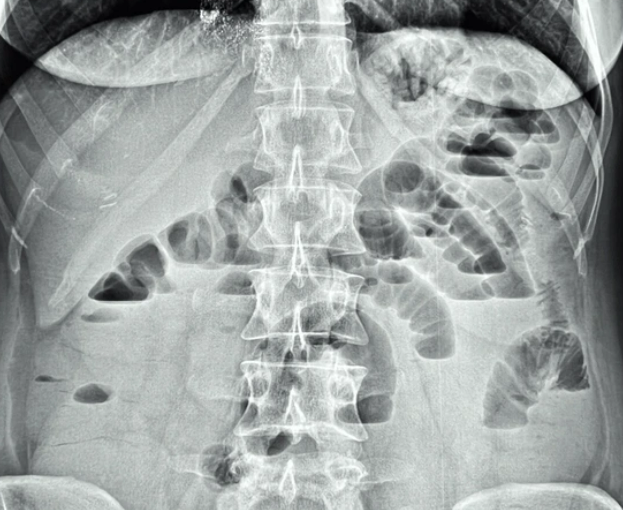

갑작스러운 복통, 혹시 마비성 장폐색일까요?

안녕하세요 오늘은 평소에 잘 모르고 지나치기 쉬운 마비성 장폐색(麻痺性 腸閉塞, paralytic ileus) 에 대해 이야기해보려고 해요.

말 그대로 장이 마비되어 장 안의 음식물과 가스, 소화액 등이 제대로 움직이지 못하고 정체되는 상태를 말해요.

마비성 장폐색은 장이 움직이지 않아서 생기는 문제예요.

즉, 막힌 것이 아니라 장의 운동이 멈춘 것이죠.